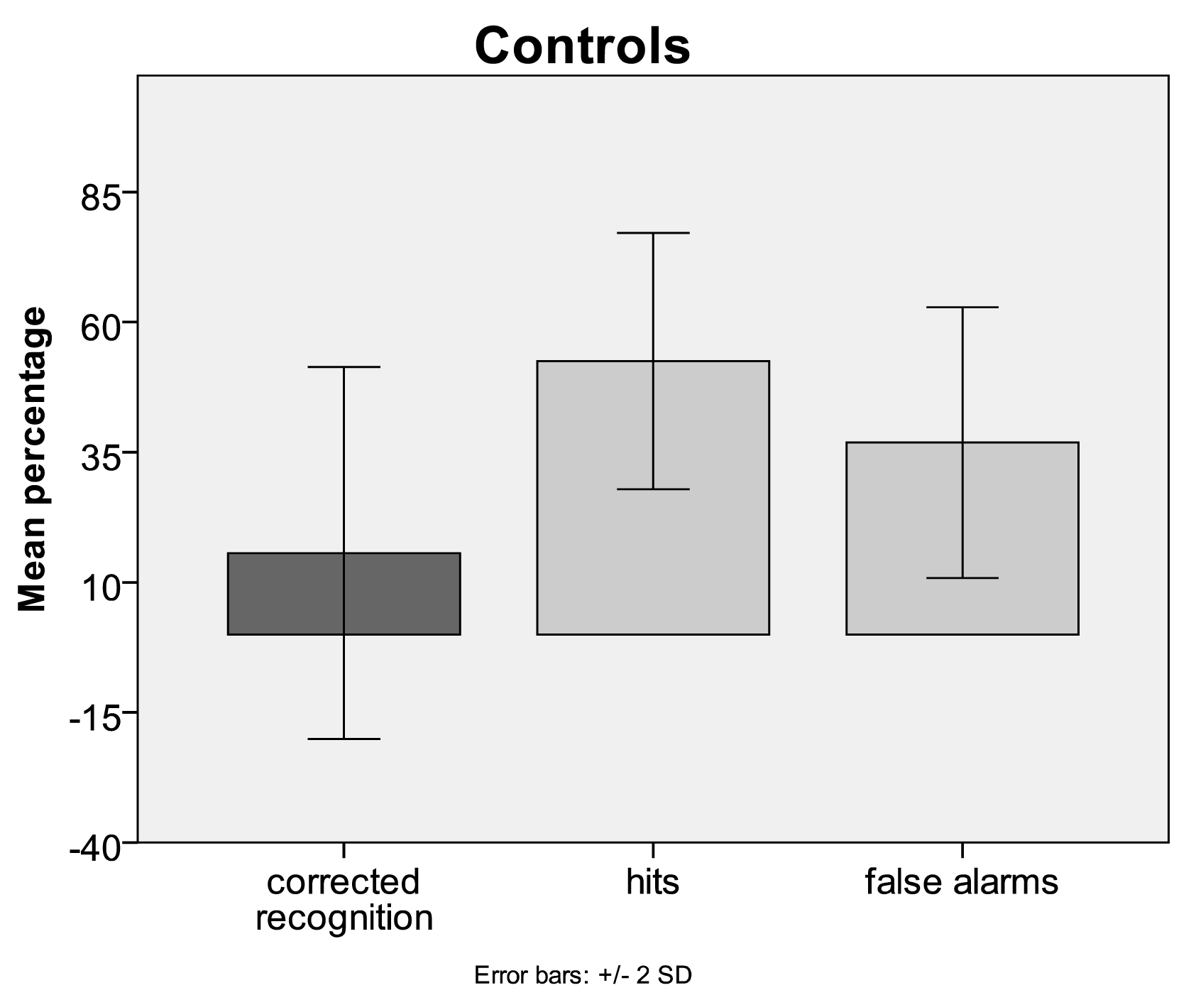

3.1. Behavioural Data

4.1. Behaviour